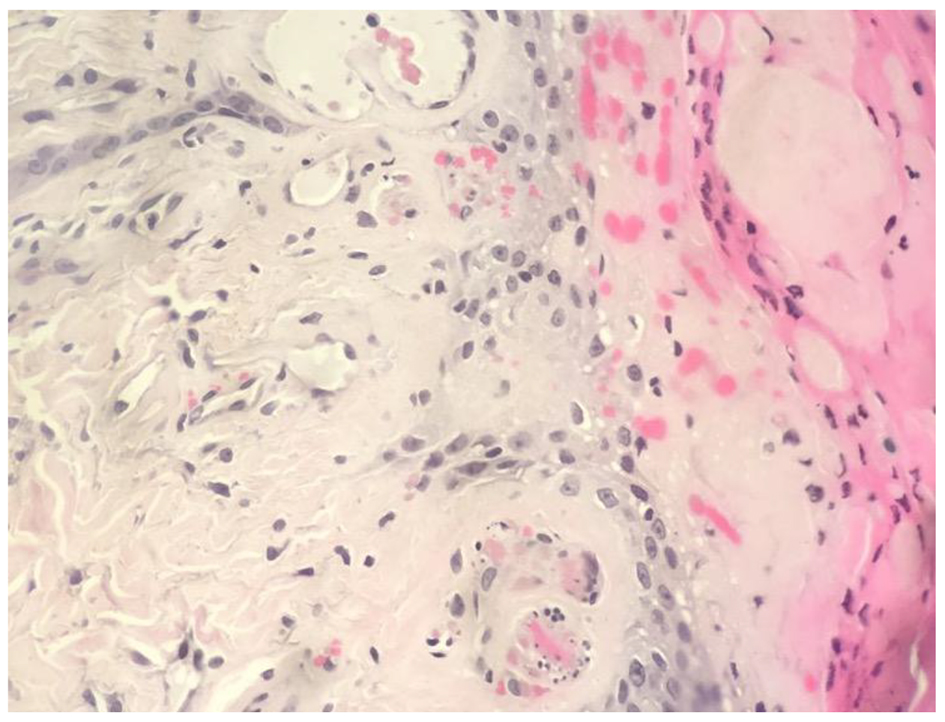

A 49-year-old Caucasian male with ESRD on hemodialysis presented to the emergency department with complaints of lower extremity pain and non-healing ulcers. Over a 3-month period, he presented to multiple medical providers complaining of lower extremity ulcers, which would not heal and were causing him debilitating pain. The patient reported being unable to walk more than a few steps without intense pain. The patient was previously diagnosed with peripheral vascular disease and lower extremity cellulitis, which upon further clinical and laboratory evaluation (Table 1), a skin biopsy was performed and it showed typical vascular changes of calciphylaxis (Fig. 1). The patient was administered sodium thiosulfate upon diagnosis and in the following weeks, displayed a marked improvement. The patient reported being able to bear weight on his lower extremity without excruciating pain and in addition, the ulcers displayed signs of healing with less induration and inflammation on the borders with continued treatment (Fig. 2). During admission, the patients’ laboratory values were closely monitored and wound management was consistently consulted.

![]() Click for large image | Figure 1. Biopsy findings. The histological section demonstrates fibrin thrombi within small blood vessels and ischemic necrosis of the epidermis, consistent with calcific uremic arteriolopathy (CUA). |